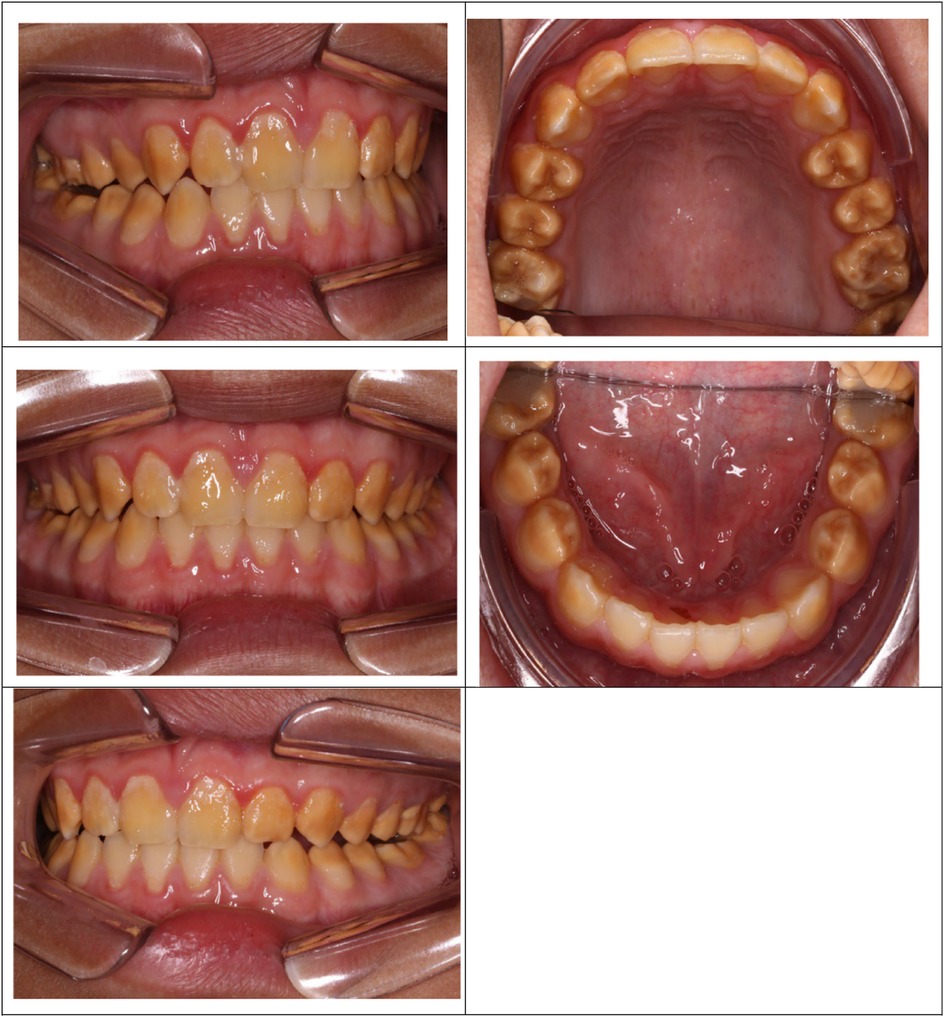

A cluster of Māori children in Northland (New Zealand) are known to have a moderate-to-severe hypo-maturation form of AI known as “Polynesian Amelogenesis Imperfecta” (or Poly AI) which is found in people of Polynesian ancestry, including New Zealand Māori (6–9). Poly AI is characterised by a bilaterally symmetrical hypo-mineralised dentition, mottled or uniformly yellow to brown in colour, with an anterior to posterior gradient in severity. Figures 1, 2 show typical Poly AI cases. Its prevalence in the wider New Zealand Māori population and other Polynesian populations is unknown. Its occurrence in the primary dentition is also poorly understood, possibly due to limited phenotypic expression in that dentition. The chalky nature of the teeth predisposes to post-eruptive breakdown and hypersensitivity with a high associated treatment burden and poorer oral health. While some of the anterior dentition may be only mildly affected, this is not always the case, and the canines and premolars (which are within the smile line) can have poor aesthetics.

Figure 2. Poly AI case showing bilaterally symmetrical hypo-mineralised dentition, with mottled uniformly yellow to brown discoloration and an anterior to posterior gradient in severity.